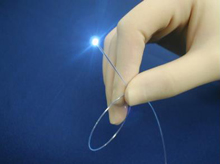

血管内視鏡

光ファイバーを挿入した内視鏡カテーテルを用いて血管内を観察することが可能な装置です。血管の性状を肉眼的に評価できるため、生体内における病理診断に匹敵する機能を有しています。冠動脈プラークの性状評価や血栓の有無、植え込まれたステントの状態評価などを直視下で行うことが可能です。

さらに大動脈内を内視鏡で観察することも可能であり、CTやMRIでは判定が困難な大動脈の動脈硬化性状を詳細に診断・鑑別することも可能です。

血管内視鏡での画像